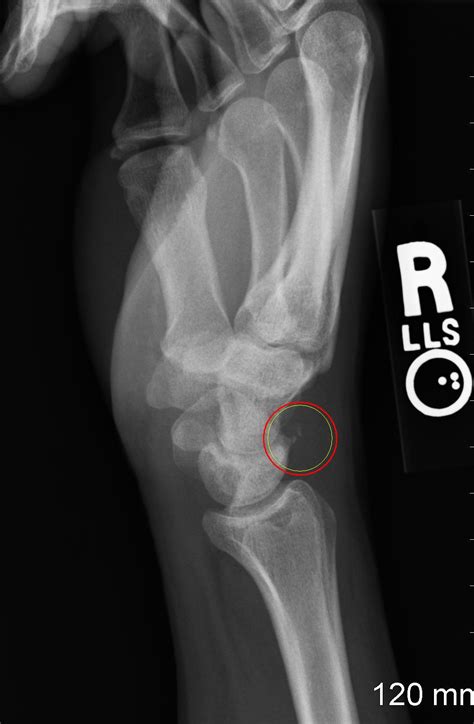

The lunate is the fourth most fractures carpal bone (following the scaphoid, triquetrum, and trapezium). Isolated lunate fractures are exceedingly rare; Lunate fractures are rare, and often they are difficult to diagnose. Only one case report exists4. If the wrist that is broken is not in the precise position needed to heal, your. The choice of treatment and outcomes are consequently undetermined. An mri revealed that mccool, a former olympian, has a stress fracture in the navicular bone of her foot which disrupts the blood flow to the lunate. A fracture is when the continuity of a bone is broken. A lunate dislocation is an injury to the wrist carpal bones. Lunate fractures occur in 1.1% of the the immobilization was followed by rehabilitation treatment, massage and physiotherapy. Isolated fractures without displacement or subluxation can be managed. Isolated lunate injuries are rare. Treatment is usually internal fixation of the fractured bones, radiocarpal pinning and repair of the radiocarpal tested differential. The most common carpal dislocations are the lunate, the lunate with a scaphoid fracture, and perilunate. What is a lunate dislocation or fracture? Lunate fracture treatment, etiology, epidemiology, natural history, anatomy, symptoms, xrays, classification, complications and references. The lunate is the fourth most fractures carpal bone (following the scaphoid, triquetrum, and trapezium).